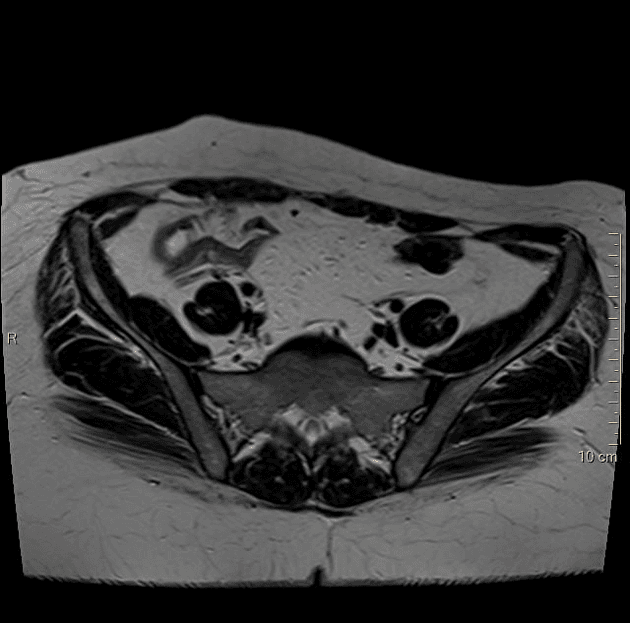

Lạc nội mạc tử cung - dấu hiệu mũ nấm

Hai tổn thương có tín hiệu trung bình đến thấp trên hình ảnh cộng hưởng từ T2 (T2WI), liên quan đến thành trước của đoạn trực tràng 1/3 trên, với dấu hiệu "mũ nấm" (mushroom cap sign) điển hình của lạc nội mạc tử cung.

Một tổn thương lạc nội mạc tử cung khác được quan sát thấy ở thành sau bên trái của đoạn âm đạo 1/3 trên.

Không thấy hạn chế khuếch tán (restricted diffusion) trên các tổn thương này, nhưng chúng có tăng quang sau tiêm thuốc cản quang (post-contrast enhancement).

Tử cung to, có nhiều u xơ (fibroids) với kích thước khác nhau, u lớn nhất nằm ở thành trước.

Vùng nối (junctional zone) tương đối dày lên, kèm các tổn thương tăng tín hiệu trong cơ tử cung (hyperintense myometrial foci), gợi ý lạc nội mạc tử cung trong cơ (adenomyosis).

Trường hợp này rõ ràng thể hiện dấu hiệu mũ nấm điển hình, đại diện cho các ổ lạc nội mạc tử cung bám trên bề mặt đại tràng sigma-trực tràng (rectosigmoid colon).

Lạc nội mạc tử cung - dấu hiệu mũ nấm (endometriosis - mushroom cap sign)

- "Dấu hiệu 'mũ nấm' trên cộng hưởng từ (MRI) là hình ảnh đặc trưng của các ổ lạc nội mạc tử cung bám vào đại tràng sigma-trực tràng, thể hiện khối u lồi tròn, hướng vào lòng ruột."

- "Các tổn thương lạc nội mạc tử cung thường có tín hiệu trung bình đến thấp trên hình ảnh cộng hưởng từ trọng T2 và tăng quang sau tiêm thuốc, không có hạn chế khuếch tán."